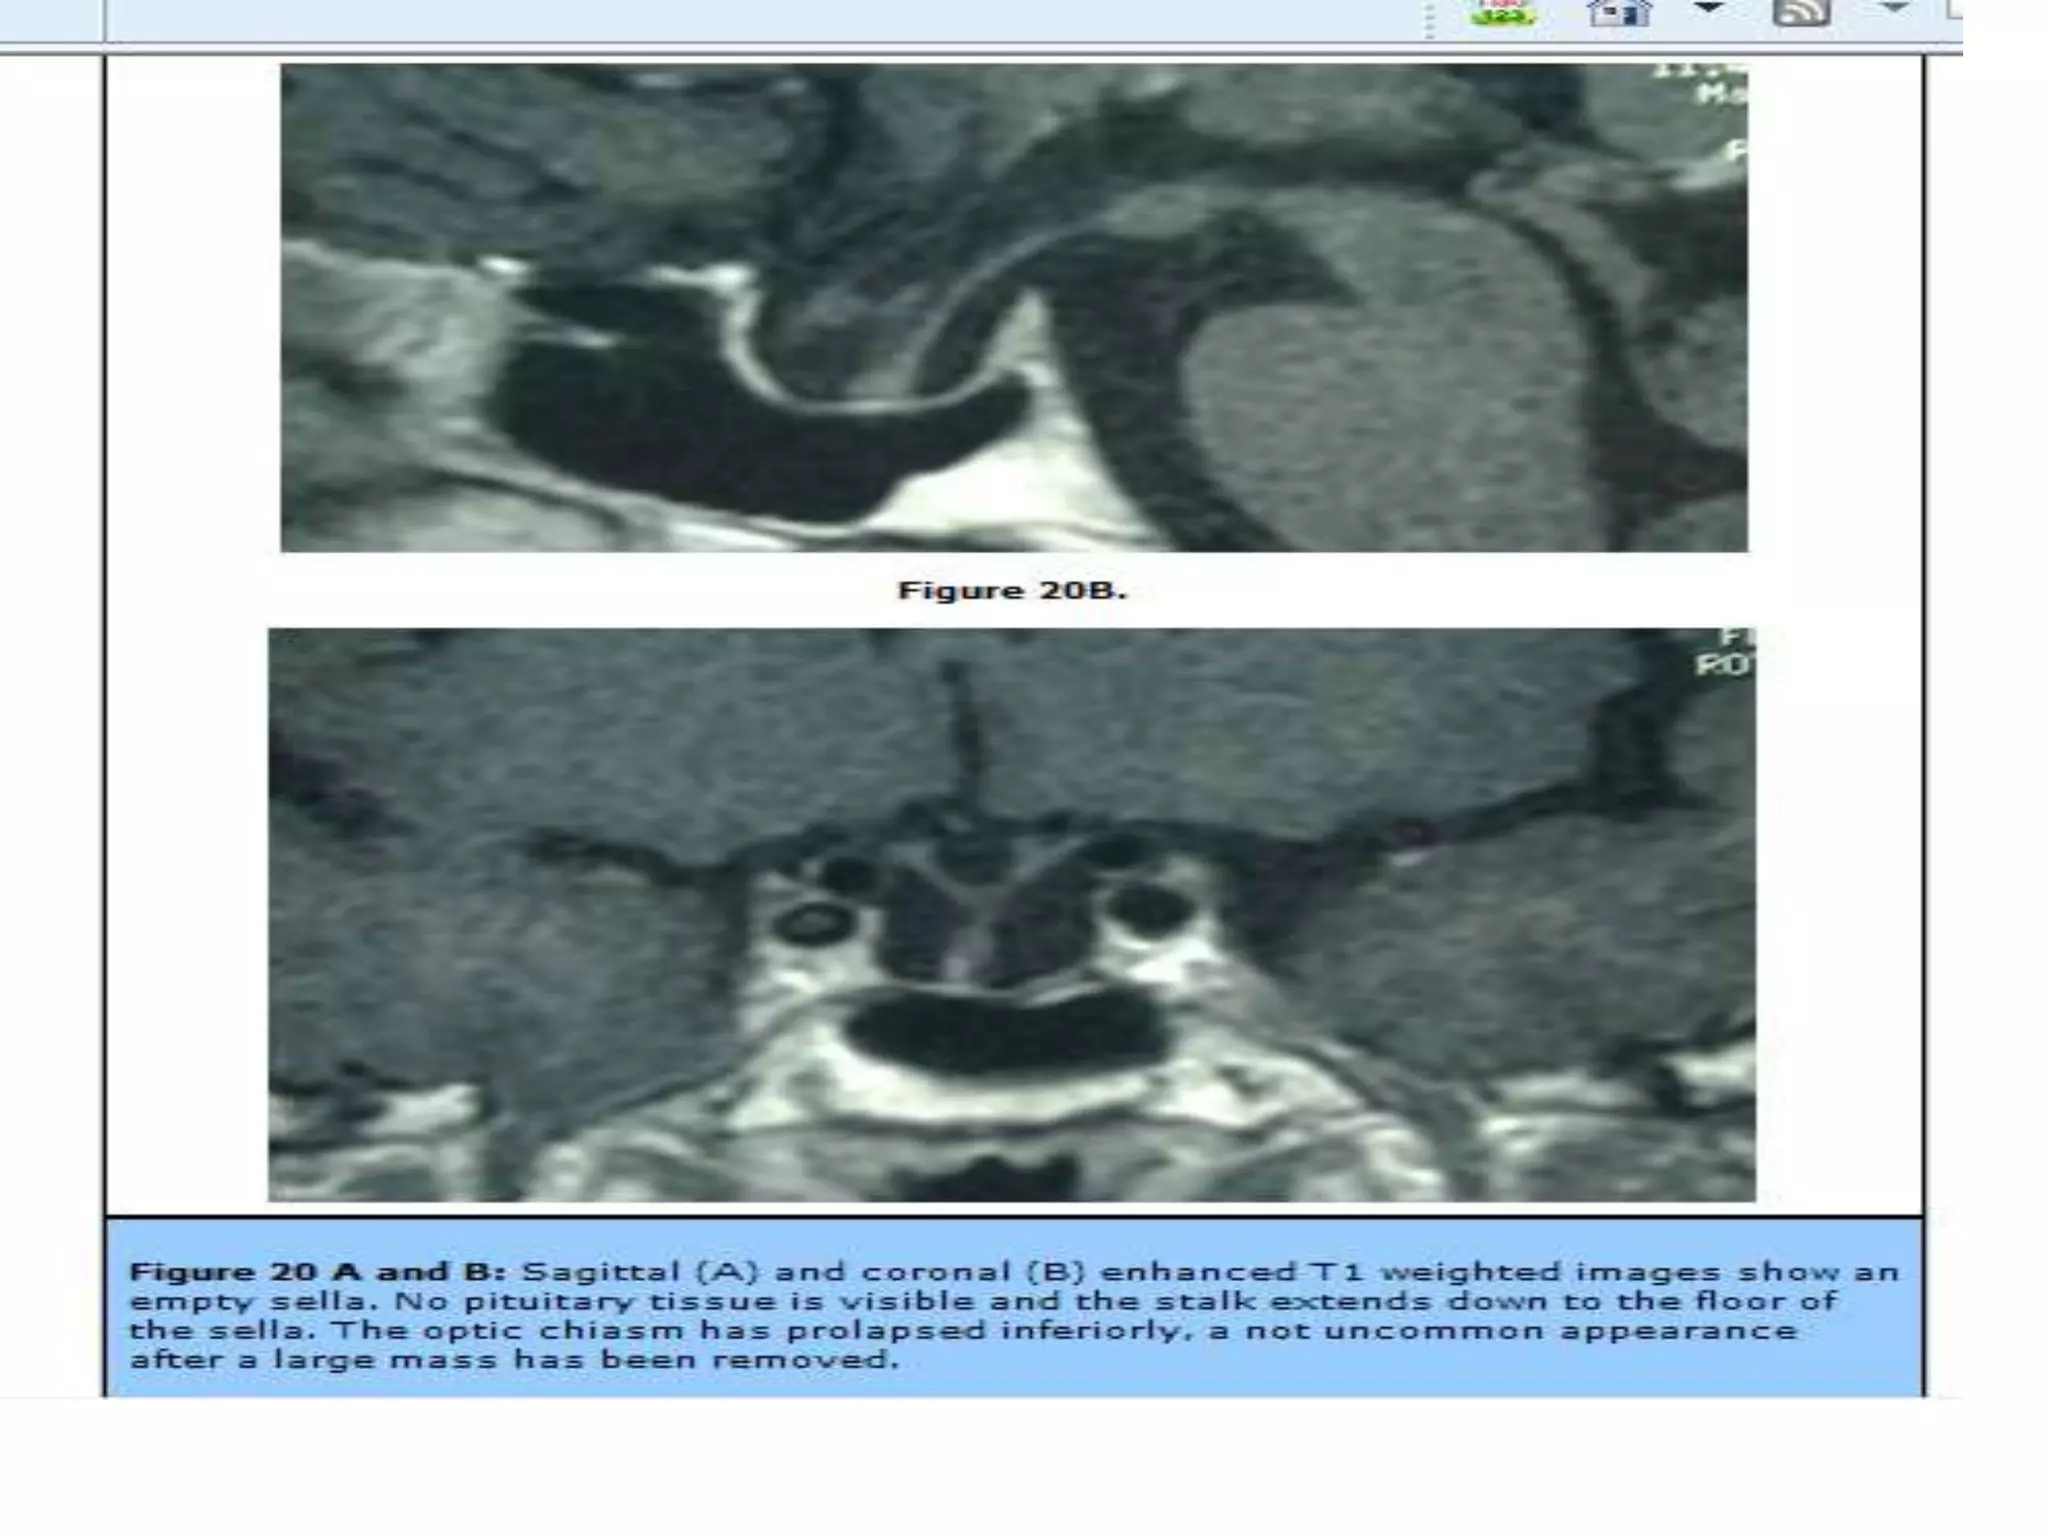

Figure 13: Sagittal T1 weighted unenhanced (A) and coronal enhanced (B) images showing a partially cystic

craniopharyngioma. This is a large complex suprasellar mass which extends down into the pituitary fossa and up to deform the

third ventricle. It is of mixed signal intensity and the solid components enhance after contrast. (B) There are patchy areas of

high signal before contrast (A) which represent the cystic components with a high protein/ lipid content.